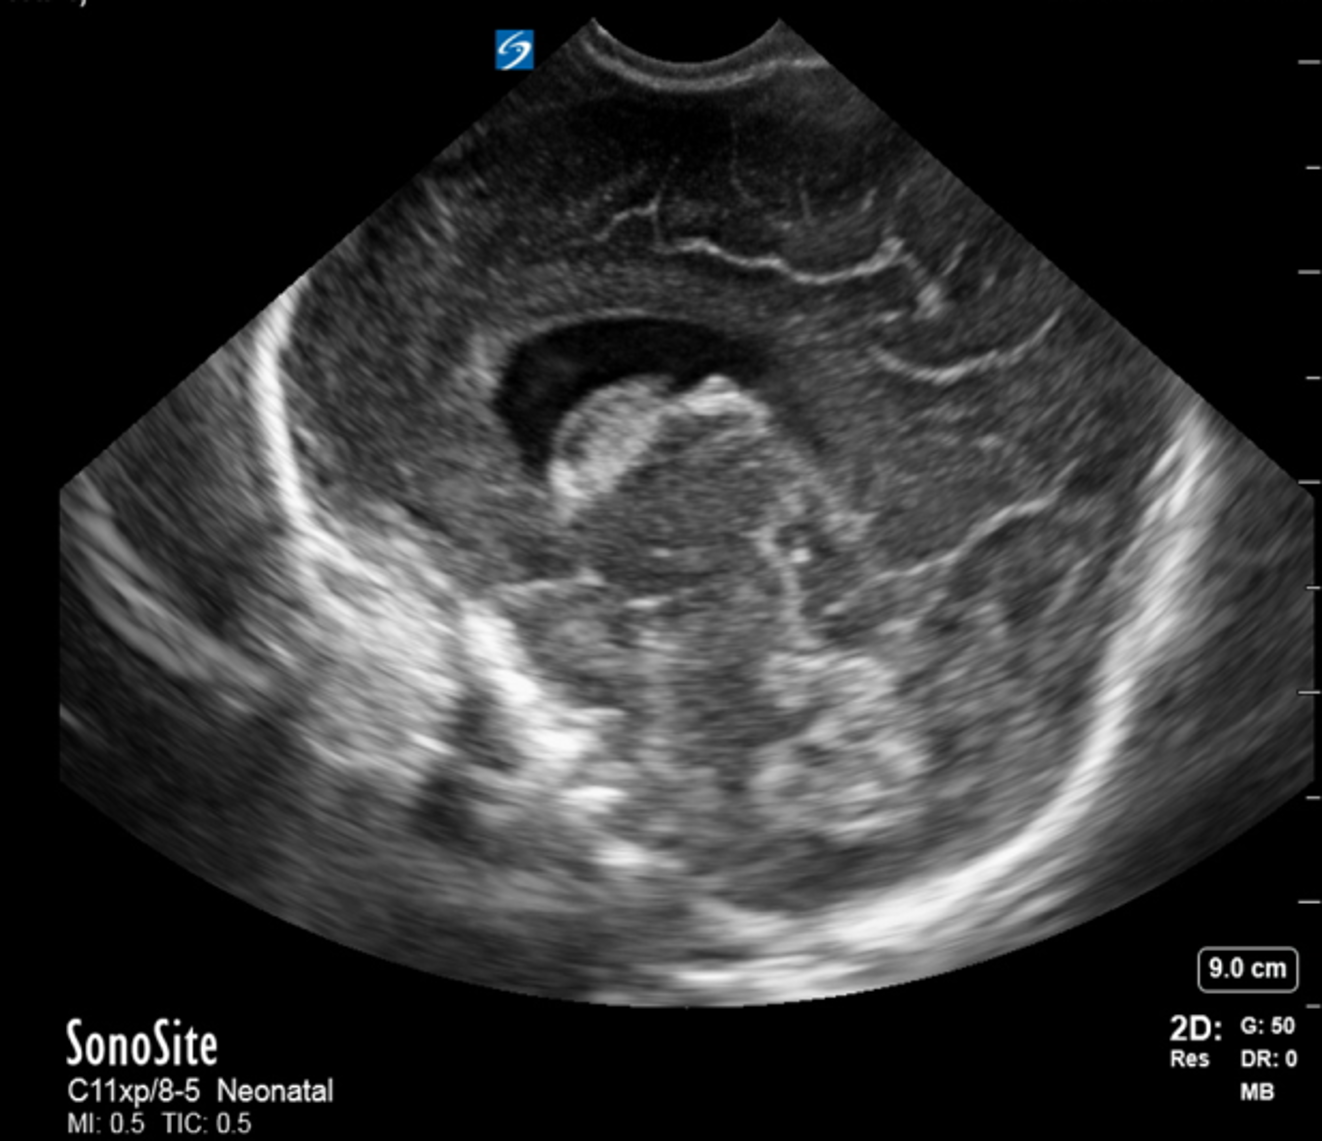

Neonatology Grade 2 IVH Sagittal 1 Image